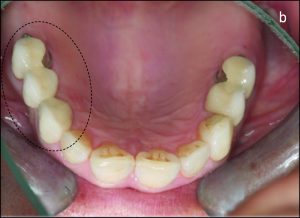

The use of direct retainers on isolated abutment teeth in distal extension PRD cases usually accelerates the destruction of the periodontium, leading to tooth loss. For this reason, it is recommended to place rests on isolated teeth and not to use direct retainers. Another option is restoration of the modification space with a fixed partial denture and splinting of the teeth (Figures 10-15).